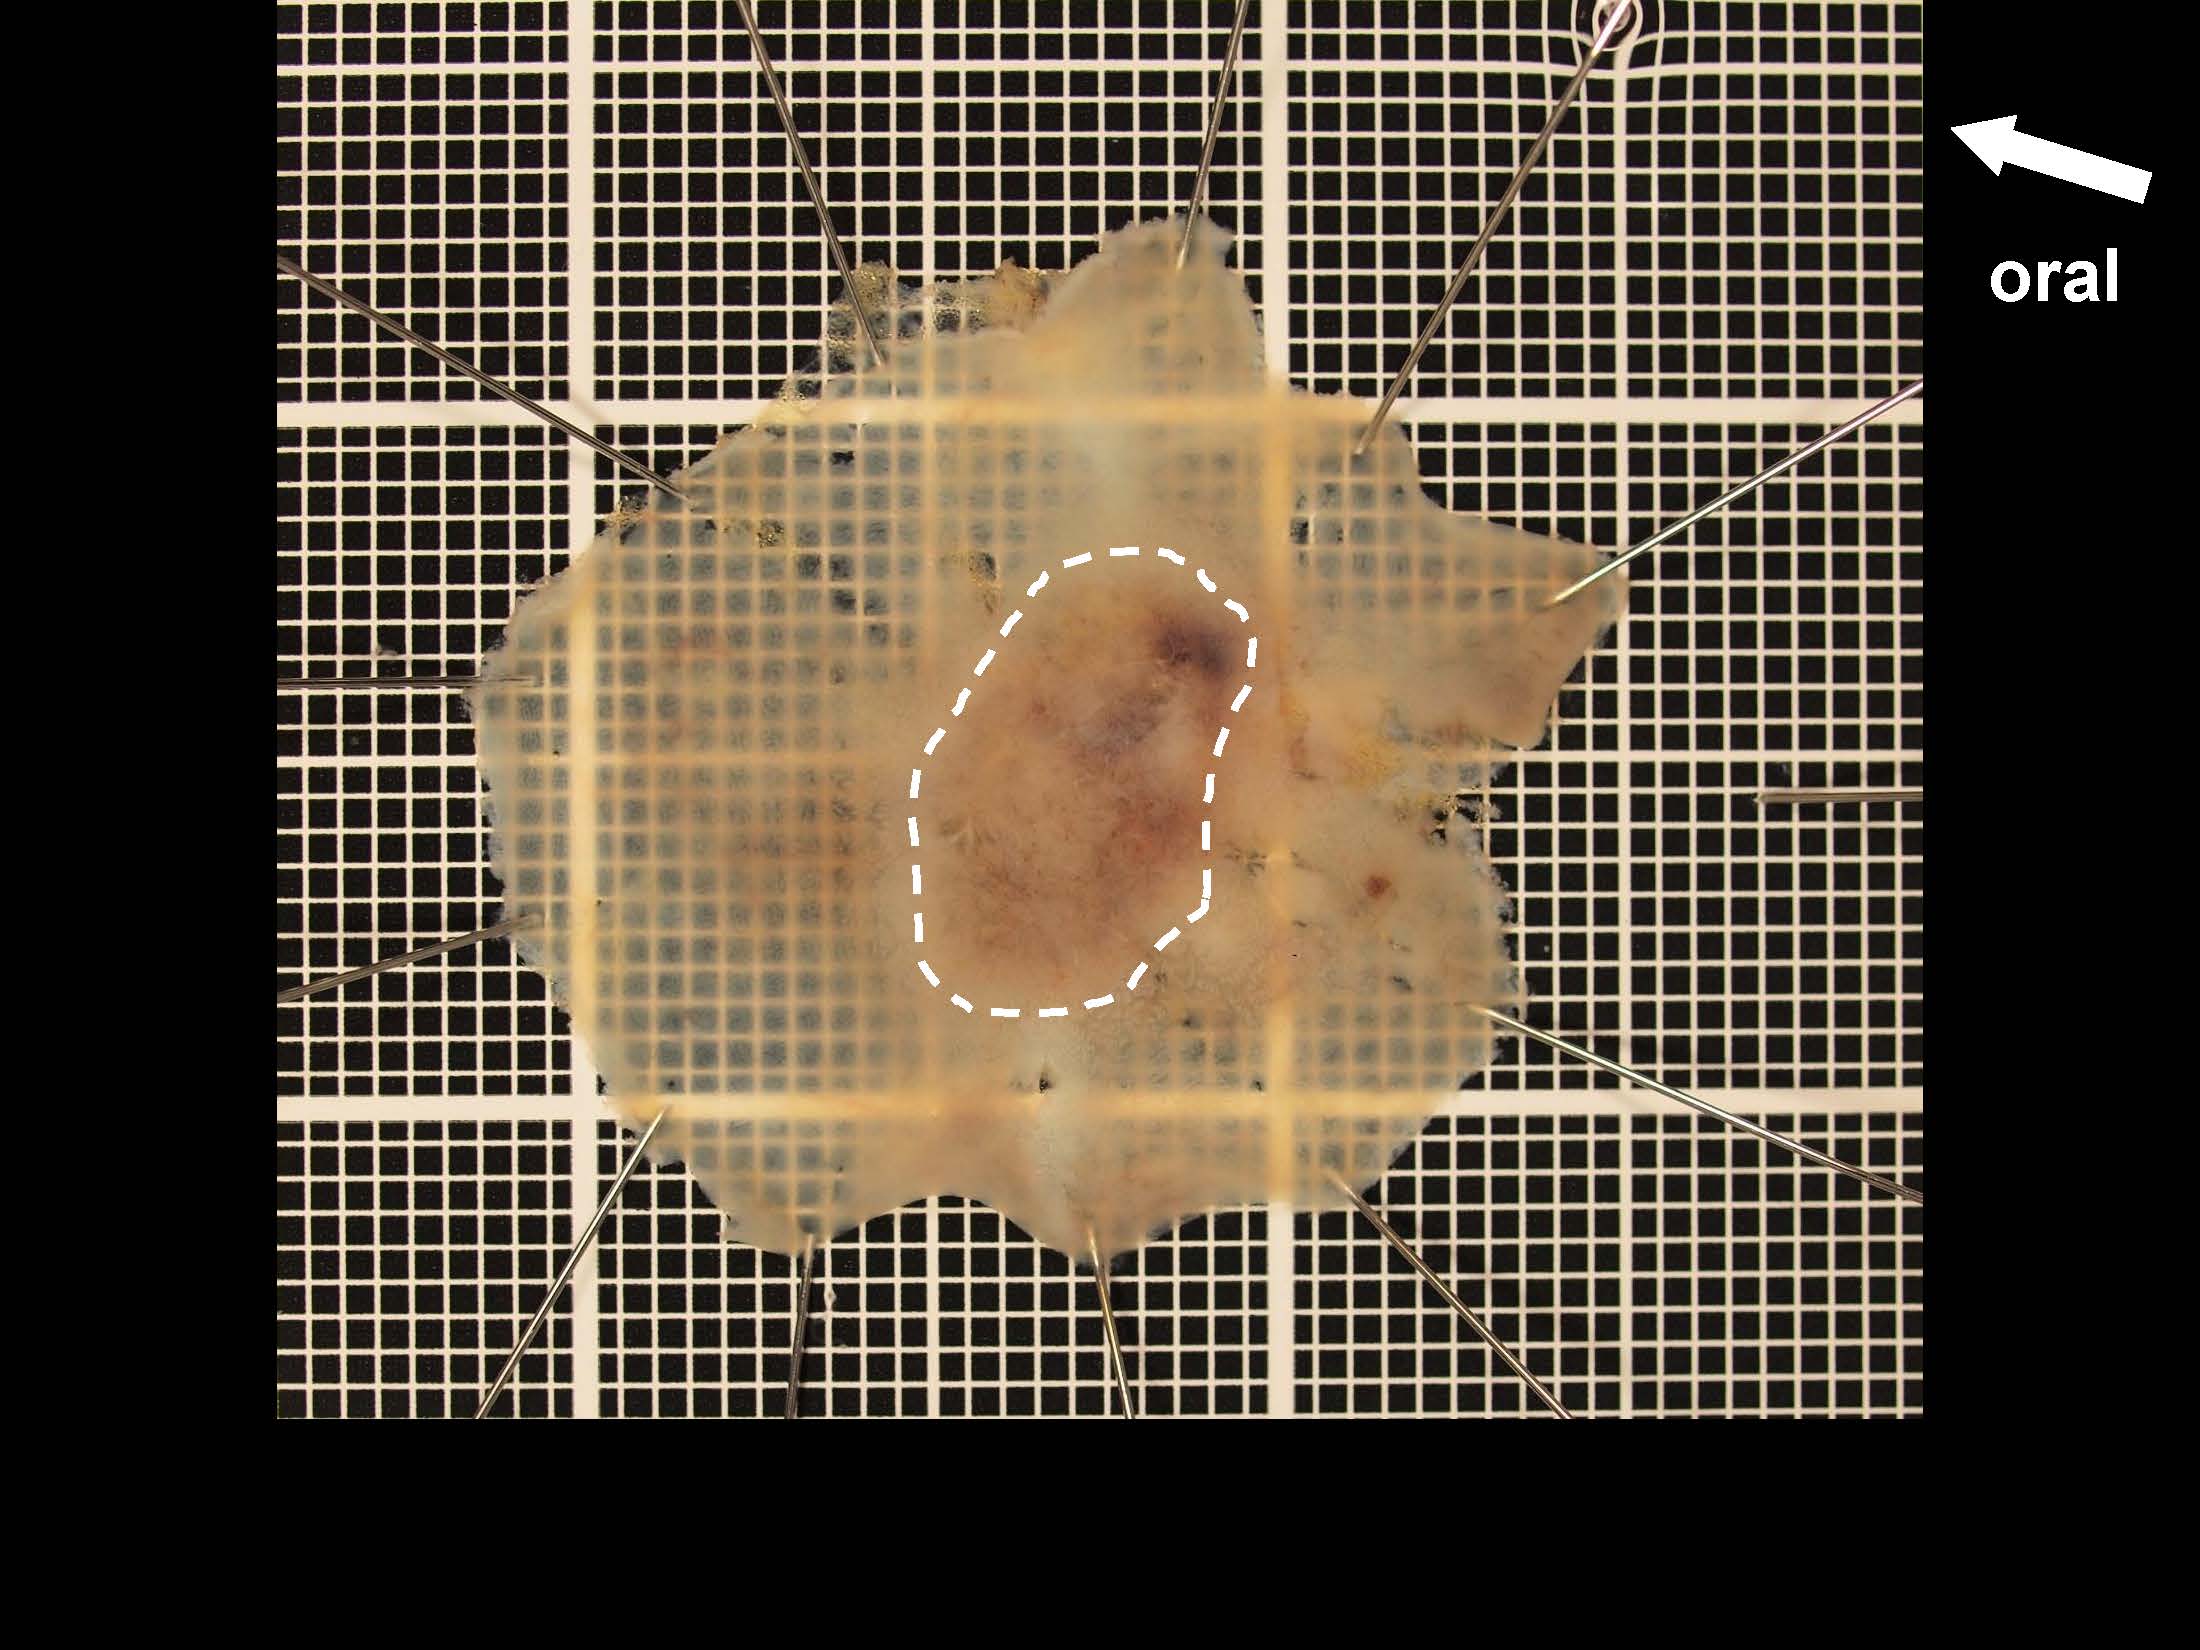

消化管Mapping~大腸~ 2021.10.27

消化管Mapping~大腸~

内視鏡検査・治療

消化管Mapping